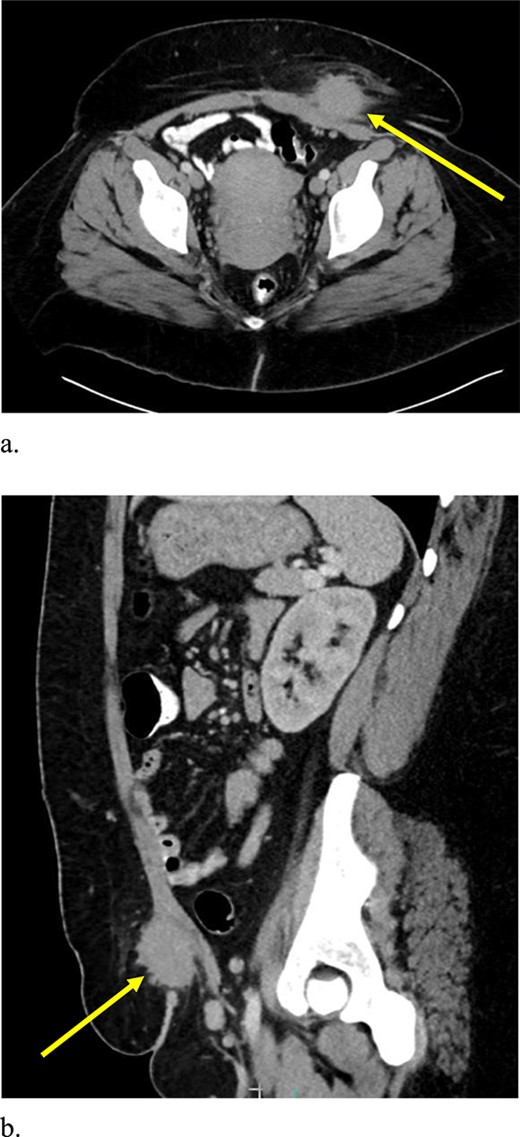

Computed tomography (CT) scan demonstrated a slightly larger, rounded mass with irregular, spiculated margins in the subcutaneous fat of the left ventral pelvis with fat stranding measuring 4.2 × 4.1 × 3.7 cm (Fig. 3). CT-guided biopsy of the mass was performed and revealed endometriosis. The decision was made to take the patient to the operating room for elective resection.

Computed tomography axial (a) and sagittal (b) views of a 4.2 × 4.1 × 3.7 cm enhancing, irregular mass on the abdominal wall (arrow) suggestive of AWE.